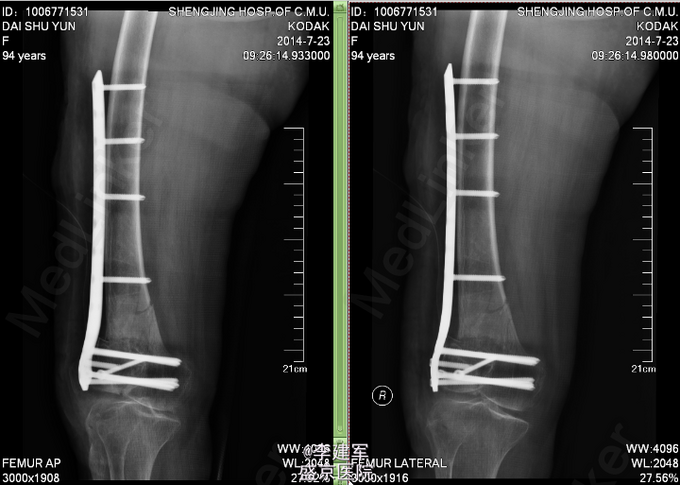

患者性别:女。年龄:94岁 主诉:摔倒后右大腿疼痛肿胀活动受限7小时 患者及其家属自述患者 弯腰拾衣物,起立时一过性意识不清,摔倒,摔倒后意识清楚,右大腿部疼痛肿胀,活动受限,被家属急送往我医院,经检查诊断为"右股骨髁上骨折",收入我科,患者伤来无头痛及发热,无咳嗽咳痰,无腹痛及恶心呕吐,饮食睡眠可,二便正常。

专科查体:右股骨石膏固定中,肿胀,压痛(+), 活动受限,骨擦感及异常活动存在,右下肢无明显麻木,右足趾可活动,足背动脉可触及。 完善心电图,肺部CT,生化检查等,查无手术禁忌症。择期手术治疗

右股骨髁上粉碎性骨折 患者高龄,完善心电图,肺部CT,生化检查等,查无手术禁忌症。择期手术治疗。 手术拟行右股骨髁上粉碎性骨折闭合复位内固定术。 决定使用Liss钢板

患者高龄选用Liss钢板做闭合复位,减小手术创口。